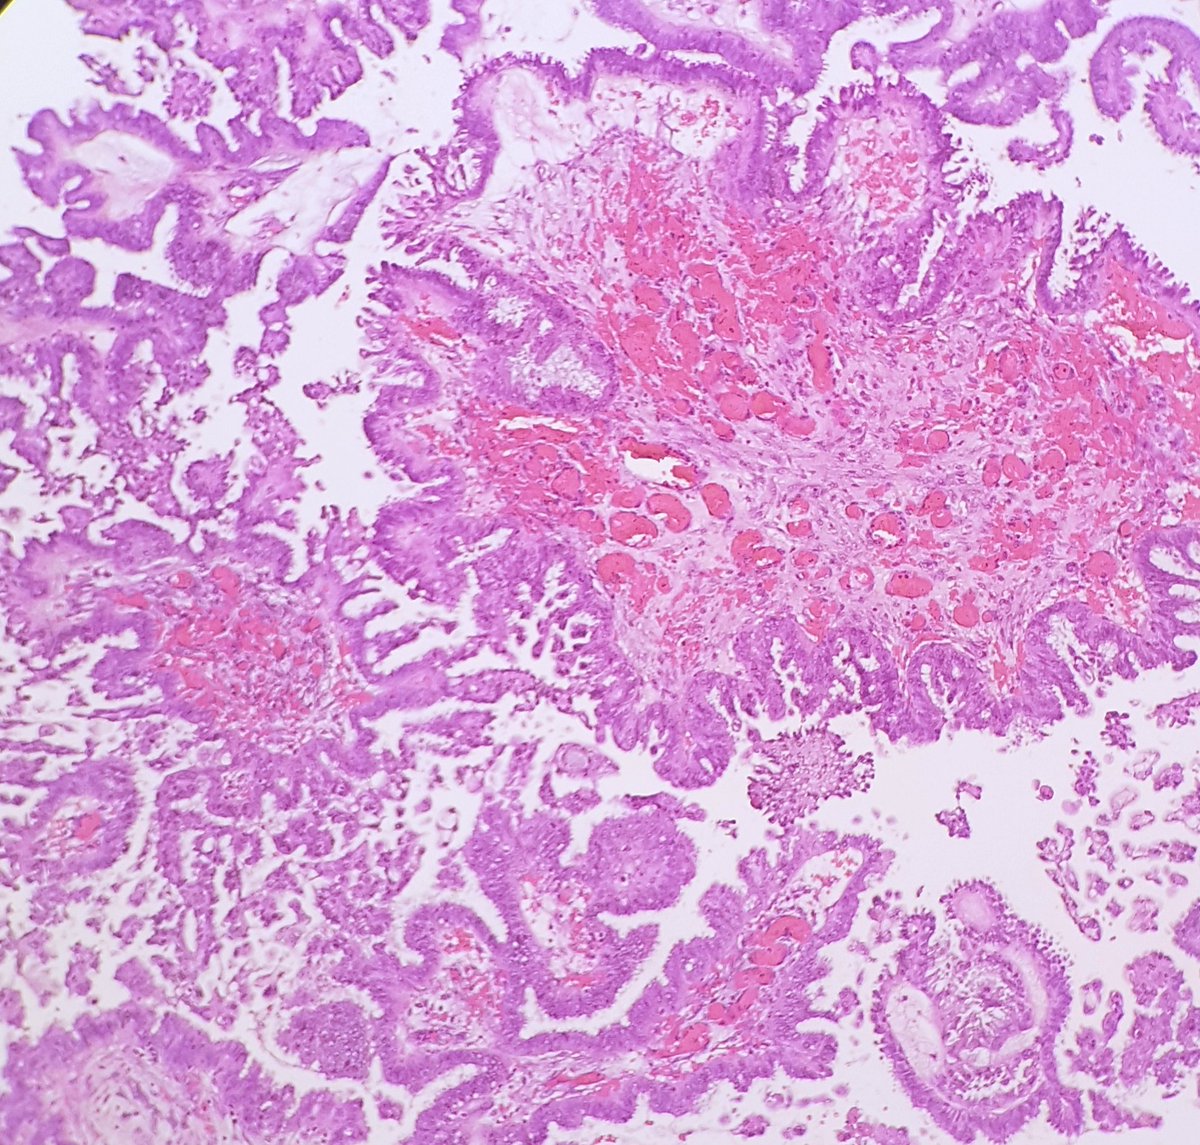

The repeated branching of this ovarian tumor reminds me of coral.

#pathology#fractalsinnature